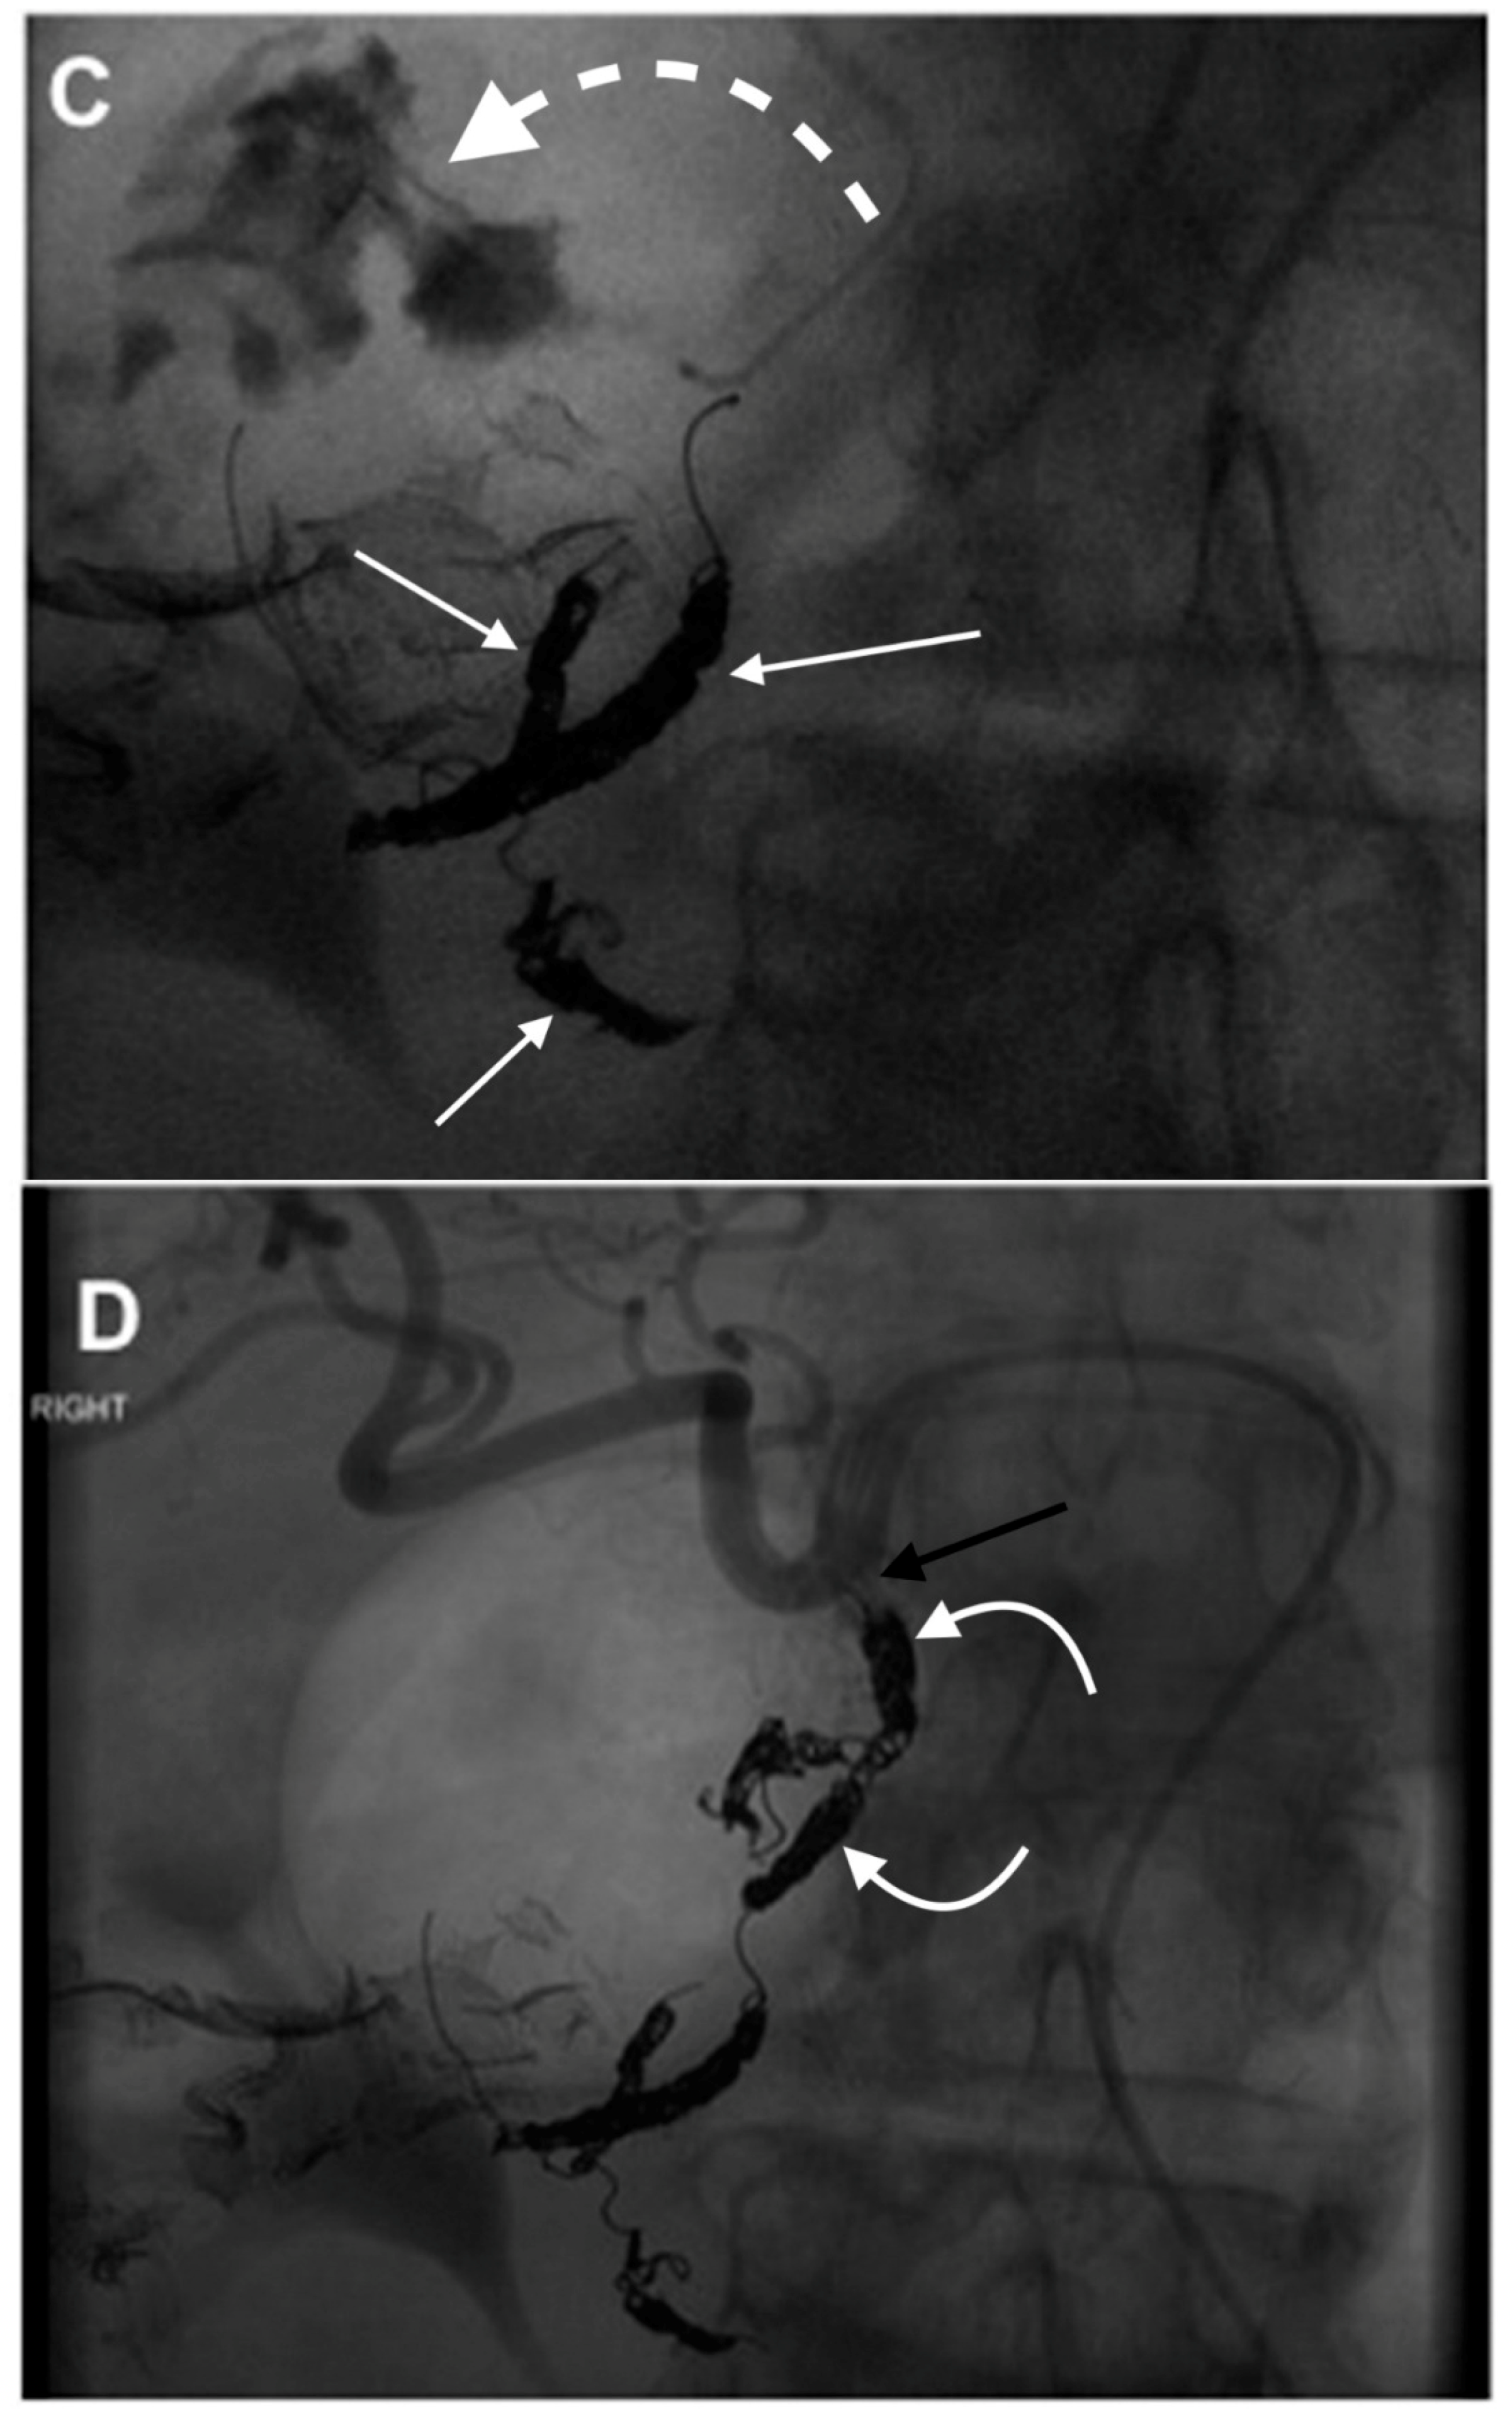

- Anil, G.; Tan, A.G.; Cheong, H.W.; Ng, K.S.; Teoh, W.C. Emergency gastroduodenal artery embolization by sandwich technique for angiographically obvious and oblivious, endotherapy failed bleeding duodenal ulcers. Clin. Radiol. 2012, 67, 468–475. [Google Scholar] [CrossRef] [PubMed]

- Enriquez, J.; Javadi, S.; Murthy, R.; Ensor, J., Jr.; Mahvash, A.; Abdelsalam, M.E.; Madoff, D.C.; Wallace, M.J.; Avritscher, R. Gastroduodenal artery recanalization after transcatheter fibered coil embolization for prevention of hepaticoenteric flow: Incidence and predisposing technical factors in 142 patients. Acta Radiol. 2013, 54, 790–794. [Google Scholar] [CrossRef] [PubMed]